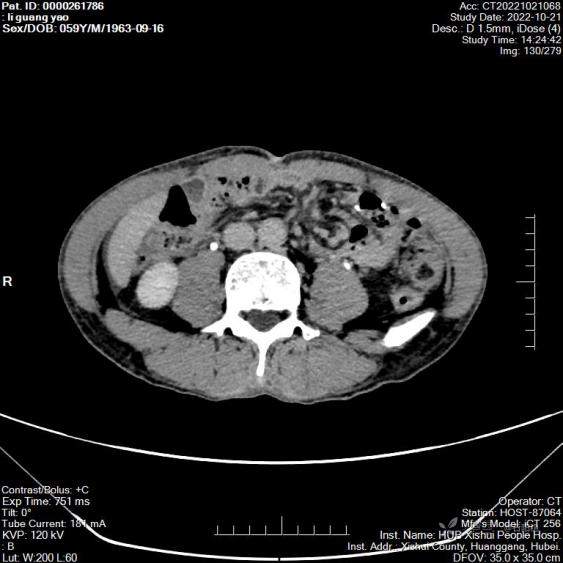

丁香医小白 推荐病例1:患者男,59岁,因“腹痛3天”于2022年10月19日入院。既往于2022年7月因胃癌在武汉同济医院行腹腔镜胃手术,具体不详,入院查体 BP101 / 68 mmHg、HR 46次/分、R 20次/分、T 36.3 ℃。腹微隆,中上腹可见一纵行手术瘢痕,上腹剑突下有轻压痛,无反跳痛,肝脾肋下未及,双肾区无叩击痛,肠鸣音正常,2022-10-19 CT平扫 1、胃术后改变。2、肝脏、胆囊、脾脏、胰腺及两侧肾脏CT平扫未见明显异常。3、腹腔内小淋巴结显示。4、盆腔少量积液。5、下腹部部分肠管、血管呈漩涡状。 入院后考虑肠扭转,入院后完善腹部增强CT,并暂予保守治疗,症状未见明显缓解,遂于2022年10月23日急诊剖腹探查,术中见:腹腔如全胃切除伴胃空肠Roux-en-Y吻合术术后所见,全小肠系膜肥厚,全小肠自食管空肠吻合口后方疝入并形成扭转。术中行腹腔镜下腹内疝松解还纳术+修补术。术后诊断:彼得森型肠系膜裂孔疝,术后恢复可,并于术后第5天(2022.10.28)顺利出院。

第一例患者CT视频(上传在第二例患者上了)